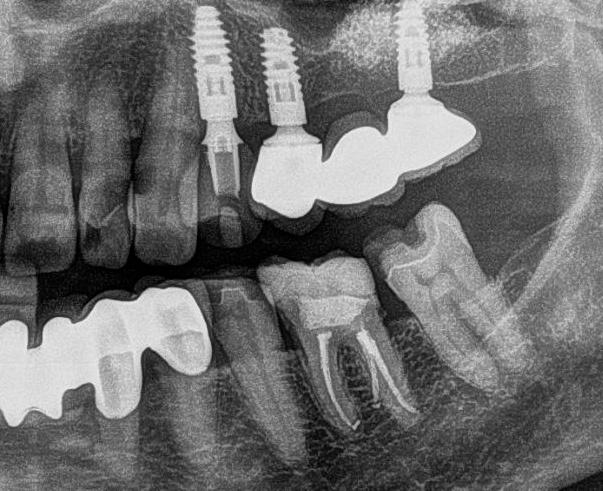

1. ábra: Műtét előtti fogászati panorámafelvétel, amelyen a hiányzó felső állcsont jobb első premolárisát és a szabad véggel rendelkező hidat láthatjuk. — 2. ábra: Az implantátum méreteinek megtervezése

Az implantáció egy biztonságos és megbízható módszer a hiányzó fogak pótlására. Az elmúlt néhány évben az implantológia jelentős fejlődésen ment át a bioanyagok, a kezelési technikák, illetve a kapcsolódó fogászati eszközök terén. Az implantológia digitalizációja is kiemelkedő előrelépéseket mutat. A fogorvos már a műtét elvégzése előtt képes előre megtervezni

és vizualizálni a kívánt eredményt, ezáltal hatékonyabb az orvos–páciens közötti kommunikáció, illetve a páciens könynyebben dönt a kezelés mellett. A kiszámíthatóság javításának másik szempontja, hogy a kezelés tervezése során kiemelt jelentőséget tulajdonítsunk a lágyszöveteknek. Az implantátumbeültetés hosszú távú sikere számos tényezőtől függ, többek között az implantátum körüli szövetek egészségétől. Mindent meg kell tenni a megfelelő implantátum körüli zárás érdekében. A következő esetleírás a lágyszövetmenedzsment és a teljesen digitális protetikai munkafolyamat kombinációját mutatja be 4-es típusú implantátumbeültetés során.

Egy fiatal páciens jelentkezett nálunk, akinek eltörött a szabad véggel rendelkező hídja (1. ábra). A hiányzó, első premoláris fog esetén implantációs pótlást javasoltunk. A csontállomány értékeléséhez CBCT-vizsgálatot végeztünk, és az elemzéséhez NNT Viewert (NewTom) használtunk, és copaSKY 4×10 mm-es (bredent medical) implantátumot választottuk a fog pótlásához

(2. ábra). A lágyszövetek értékelése Seibert szerinti I. osztályú csontdefektust állapított meg (3. ábra), ezért a beavatkozáskor palatinális „tekercslebenyt” preparáltunk (palatal roll flap), és implantációt végeztünk, hogy kompenzálni tudjuk a bukkális lágyszövet-behúzódást. Megmértük a vertikális lágyszövetvastagságot, és úgy terveztük, hogy a szubkresztális implantátum beültetése összhangban legyen a biológiai szélesség kialakulásával a transzgingivális gyógyulási periódus alatt (4. ábra)

Az eljárást helyi érzéstelenítés mellett végeztük (4%-os articaine-hidroklorid 1:100 000 adrenalinnal). Papillakímélő, U alakú palatális bemetszést végeztünk, teljes vastagságú nyálkahártyalebeny preparálás történt, a lebenyt bukkálisan feltekertük (5. ábra). A lebeny bukkálisan feltekert részén de-epitelizációt végeztük el, amellyel kompenzálni tudtuk a bukkális lágyszöveti defektust. Szakaszos előfúrást végeztünk, és a bredent copaSKY 4x10 implantátumot 30 Ncm behajtási nyomatékkal helyeztük be (6. ábra). Az implantátumot 1 mm-re szubkresztálisan helyeztük be, hogy később szélesebb emergenciaprofilt tudjunk kialakítani (7. ábra). Az egyedi ínyformázó úgy készült, hogy kompozitot vittünk fel a titánbázisra, és így formáztuk a lágyszöveteket a transzgingivális gyógyulási fázis során (8. ábra). Az egyéni ínyformázó tulipán formájú, hogy kialakítsa a kívánt emergenciaprofilt. A lágyszövetet feszülésmentesen zártuk #6/0 nem felszívódó, monofil fonallal (Optilene, B. Braun Deutschland; 9. a–b. ábra). Posztoperatív röntgenfelvétel készült, ami alapján az implantátum a szomszédos fogakkal párhuzamos elhelyezést mutatott (10. ábra). Posztoperatív utasításokat adtunk a páciensnek a műtéti terület körüli szájhigiénia fenntartása érdekében. A beavatkozást követő egy héttel a varratokat eltávolítottuk, és a kezelt terület kielégítő gyógyulást mutatott (11. ábra). A 4 hónap utáni késleltetett terhelést a páciens kívánsága szerint terveztük.